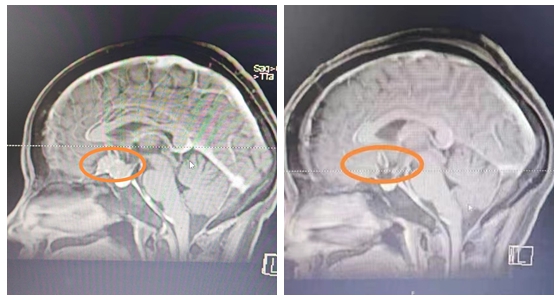

患者丁女士,3月前开始出现左眼视物模糊、视力下降并伴有头痛,多次辗转求医,但患者的视力在进一步减退,几近失明。随后,丁女士慕名来到了湘雅常德医院,头部MRI检查提示:“鞍上区占位性病变”,考虑为:鞍结节脑膜瘤。完善检查发现:肿瘤大小约2.7*2.5cm,左侧视神经受压变性,并累及垂体柄、颈内动脉。此类肿瘤手术难度非常大,风险较高,稍有不慎就可能破坏这几处神经血管结构。

手术前后对比图

经过缜密的术前讨论,4月17日,袁贤瑞教授团队在全麻下为患者实施“开颅探查鞍上区病损切除术”。在显微镜下完全切除肿瘤,双侧视神经、视交叉、颈内动脉及分支眼动脉、大脑前动脉、垂体柄等结构保留完整,手术顺利完成,现术后恢复良好,无任何神经系统并发症,无垂体功能障碍。出院时,患者及家属露出了满意的笑容。